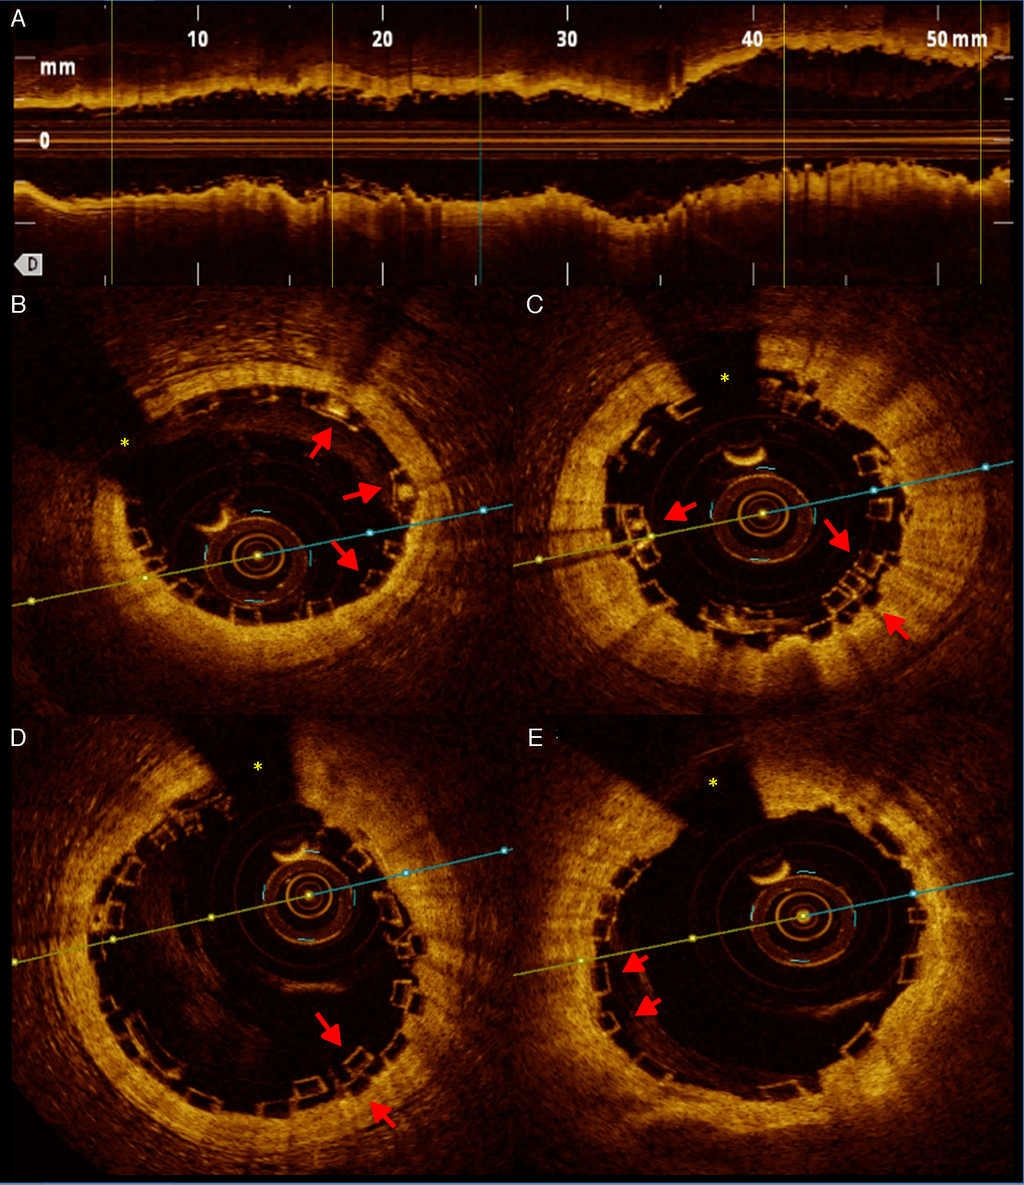

Presentamos el caso de un paciente varón de 57 años con antecedentes médicos de hipertensión arterial sistémica y que se presentó en nuestro servicio con historia de angina crónica estable. Se le realizó estudio de perfusión miocárdica con esfuerzo físico que objetivó dolor de tipo anginoso durante la prueba, y en las imágenes de medicina nuclear, isquemia miocárdica grave en la pared anterolateral. Se le realizó estudio de coronariografía diagnóstica que objetivó oclusión total crónica de la arteria descendente anterior (DA) posterior al nacimiento del primer ramo diagonal, mismo que tenía estenosis severa en su segmento proximal (fig. 1. A y B). Se preparó la lesión de la DA, predilatando con 2 balones compliantes de 1.50 × 20 mm y 2.50 × 20 mm hasta 16 atmosferas y el ramo diagonal se predilató con balón compliante de 2 × 15 mm a 12 atmosferas (fig. 1. C). En el ramo diagonal se implantó stent de cromo-cobalto y liberador de everolimus de 2.50 × 16 mm a 12 atmosferas. La lesión larga de la DA se trató con 3 DVB (Absorb, Abbott Vascular, Santa Clara, California, EE. UU.) de distal a proximal de 2.50 × 18 mm, 3 × 28 mm y 3.50 × 18 mm a 8 atmosferas, solapados mediante las guías de platino de los dispositivos. Se realizó optimización a la DA con balón no compliante de 3 × 20 mm hasta 14 atmosferas, de distal a proximal (fig. 1. D). Finalmente se realizó estudio de tomografía de coherencia óptica intracoronaria a la DA para corroborar el adecuado posicionamiento de los 3 DVB, así como la zona de solapamiento que fue de 2 mm tanto en el distal-medio como en el medio-proximal (fig. 2).

Figura 2 A) Imagen de tomografía de coherencia óptica (TCO) en el eje longitudinal, posterior a la implantación de 3 DVB. B) Corte de TCO del borde distal del primer DVB en donde se muestra el adecuado posicionamiento de los struts y los marcadores de platino (flechas rojas). Sombra de la guía intracoronaria(*). C) Corte de TCO en donde se observa el primer solapamiento del DVB distal y medio donde se observa perfecto solapamiento de 2mm y adecuado posicionamiento de los struts (flechas rojas). D) Corte de TCO donde se observa el segundo solapamiento de DVB medio-proximal (flechas rojas). E) Borde proximal del tercer DVB con adecuado posicionamiento de los struts (flechas rojas).

En nuestro caso, el tratamiento "híbrido" del ramo diagonal con stent metálico liberador de everolimus y de la DA con 3 DVB, en una oclusión total crónica larga, con contenido leve a moderado de calcio, demostramos la viabilidad de tratar este tipo de lesiones con estos dispositivos de forma segura (el paciente se mantiene sin eventos cardiovasculares mayores a 8 meses de la implantación). El resultado final exitoso, y sin malaposición de los struts del DVB fue guiado mediante tomografía de coherencia óptica. Cabe decir que, al igual que en los estudios mencionados previamente, la clave para el éxito de estos procedimientos parece ser la alta presión de expansión del DVB e inclusive el ligero sobredimensionamiento. En lo que respecta a la manera de implantar los DVB de forma solapada, estos dispositivos tiene marcadores de platino colocados en los extremos, situados a 90°. La forma más adecuada de asegurar el solapamiento recomendado de 1-4 mm se logra colocando mediante angiografía estos 2 marcadores a menos de 1 mm de distancia; en nuestro caso, las imágenes de tomografía de coherencia óptica corroboran el adecuado solapamiento de los 3 DVB. Por el momento nosotros recomendamos la utilización de alguna de las 2 técnicas de imagen intravascular disponibles en nuestro país, sin embargo en la medida que la curva de aprendizaje con estos dispositivos mejore, será viable y segura la implantación sin ayuda de ningún tipo de imagen, en casos seleccionados. La respuesta sobre si estos DVB serán el futuro inmediato en los procedimientos intervencionistas, incluyendo los síndromes coronarios agudos, parece apuntar a una afirmación; no obstante la seguridad y eficacia, los resultados en términos de revascularización de la misma estenosis, ya sea por trombosis o reestenosis, y la recuperación del vaso una vez reabsorbido el dispositivo, recuperando la fisiología y propiedades vasomotoras, hacen que se deban considerar los DVB como una nueva opción de tratamiento para los pacientes.